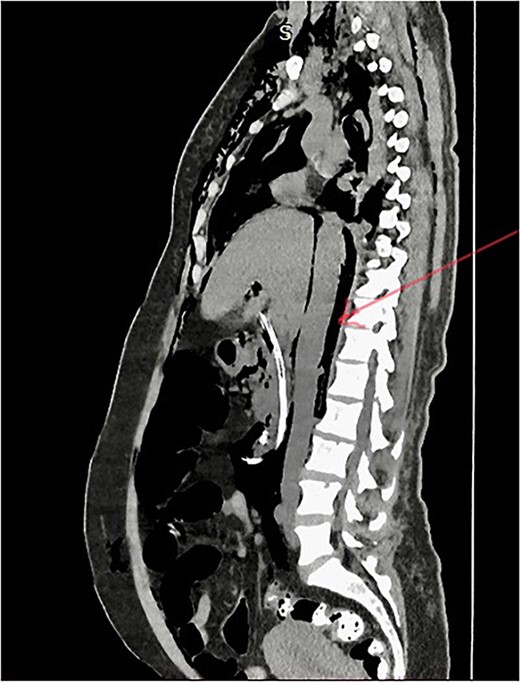

She has undergone a semi-elective ERCP in a semi-prone position, under sedation with propofol target-controlled infusion. Major papillae identified with side viewing endoscopy. Guidewire was inserted into CBD, and a cholangiogram was done. It showed dilated CBD up to 1.3 cm, mild dilated hepatic ducts, and a large radiolucent area in the distal CBD (around 1.5 cm). Sphincterotomy was done with a sphincterotome, and the ampulla was dilated up to 1.5 cm with a balloon dilator. Then, a balloon retrieval was attempted and failed, probably due to a stone sticking to the CBD wall. Then, a mechanical lithotripter was used to break the stone, but it failed, damaging the instrument. During the procedure, her oxygen saturation dropped to 75–80%, and she developed surgical emphysema in the face, neck, and upper chest region. In addition, she developed abdominal distention as well. Immediately, she underwent CBD stenting with a 12-cm, 10 French Gauge double pigtail biliary stent and changed her position to supine. Then, she was intubated with rapid sequence induction, and a nasogastric tube was inserted and transferred to the surgical intensive care unit. Post-ERCP, non-contrast computed tomography (NCCT) of the abdomen and chest showed extensive pneumo-peritoneum and retroperitoneal gas with subcutaneous emphysema (Figs 2 and 3). There was no evidence of air leakage on NCCT and no clinical features of peritonitis on subsequent days. So she was managed non-surgically with nasogastric tube (NG), nil by mouth, intravenous fluids with intravenous antibiotics. Clear fluid was started after 24 hours slowly via NG.

Post-ERCP NCCT abdomen shows pneumo-peritoneum (red arrow), pneumo-retroperitoneum, and subcutaneous emphysema (blue arrow)

Post-ERCP NCCT abdomen shows pneumo-retroperitoneum (red arrow).